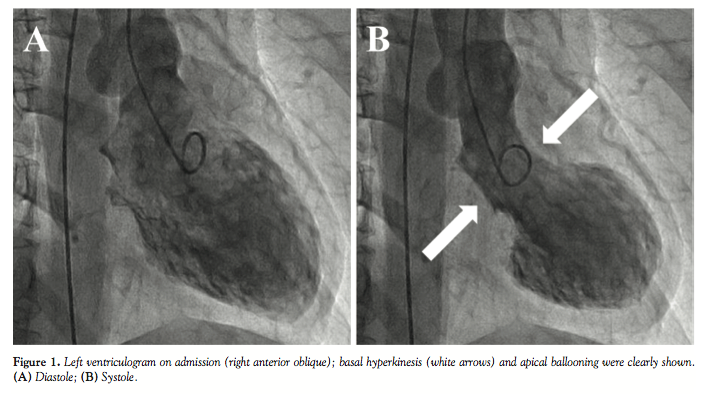

Due to the presence of complete right bundle branch block, her electrocardiogram was not decisive. The serum troponin I level was modestly elevated and transthoracic echocardiography revealed akinesis of the mid to apical left ventricle. Emergent coronary angiography showed no abnormality; however, subsequent left ventriculography showed basal hyperkinesis and apical ballooning (Figure 1A = diastole; Figure 1B = systole). The electrocardiogram showed T-wave inversion in broad leads on the day after her admission and resolved in several months. Follow-up echocardiography showed complete recovery in 2 weeks.